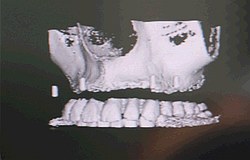

Das 3-D Modell kann virtuell gedreht und gewendet werdenAblauf während der OP Ein optischer Sensor vermisst hochpräzise die Lage von Patient und Bohreinheit. Das Navigationssystem zeigt dem Operateur über intuitiv zu erfassende Farbmarkierungen die korrekte Lage seines Bohrers in Bezug auf das zu setzende Zahnimplantat an. Das Verfahren basiert auf Infrarotlicht, das an kleinen, leichten und ergonomisch angebrachten Reflektorkörpern an Bohreinheit und Patient gespiegelt wird. Ähnlich der Wirkungsweise der menschlichen Augen werden die Reflektionsprismen von 2 Infrarotkameras beobachtet und durch Stereovision die räumliche Lage exakt bestimmt. Es befinden sich keine Kabel am Patienten, dadurch wird die Handhabung wesentlich erleichtert. Während der OP wird dem Implantologen die Abweichung zwischen Instrument und geplanter Implantatachse mit einer Genauigkeit im Zehntelmillimeter-Bereich angezeigt und dokumentiert (zur Qualitätssicherung). Das Navigationssystem erkennt automatisch die Länge des eingespannten Bohrers und identifiziert selbständig das gerade zu bohrende Zahnimplantat. Die Tiefe des Bohrers im Knochen kann der Implantologe an einem Rollbalken am Bildschirm verfolgen. Sobald die exakte Tiefe erreicht ist, ertönt zudem ein akustisches Signal. Der Patient wird zur präoperativen Planung im CT-Gerät oder DVT gelagert. Es erfolgt dann ein Spiral –CT des Kiefers mit hochauflösenden dünnen Schichten. Die gesamte Untersuchung der Radiologen in Berlin dauert einschließlich Lagerung für den Patienten ca. 2 bis 3 Minuten. Der Datensatz des Kiefers wird dann mit den Rekonstruktionsparametern weiterverarbeitet. Diese Information wird einer CD-ROM für den Patienten gespeichert und steht dann für den Operateur zur Verfügung.